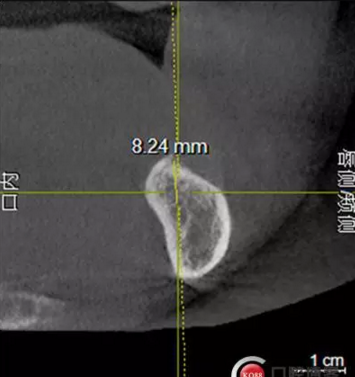

檢查:上頜無(wú)牙頜假牙穩(wěn)定性尚可,下頜3435364243殘根;33殘冠1-2度松動(dòng),其他牙齒缺失;CBCT檢查:下頜牙槽骨前牙區(qū)骨高度足,后牙區(qū)骨高度最低為8mm,骨寬度足。

1)術(shù)前檢查,拍攝臨床照片及CBCT檢查,制取活動(dòng)義齒參考模型,指導(dǎo)后期最終修復(fù)的牙齒排列

2)術(shù)前準(zhǔn)備及手術(shù)過(guò)程,測(cè)量血壓及血糖,簽種植知情同意書(shū);嚴(yán)格遵循無(wú)菌操作,局麻下采用微創(chuàng)技術(shù)于323436分別植入osstem4.0X10,4.0X10,4.5X7; 434446分別植入osstem4.0X1O,4.0X10,4.5X7.初期穩(wěn)定性均達(dá)到了35N.CM以上;嚴(yán)密縫合,止血,種植體位點(diǎn)和方向與設(shè)計(jì)一致。